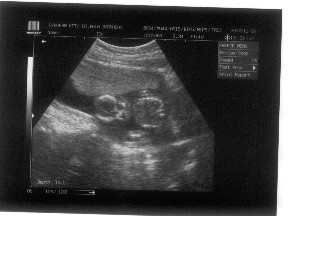

Gratulálok!!!!

Jó egészséget, sok tejcsit kívánok!Tényleg gyere és mesélj, és képeket is kérünk!!!!!!!